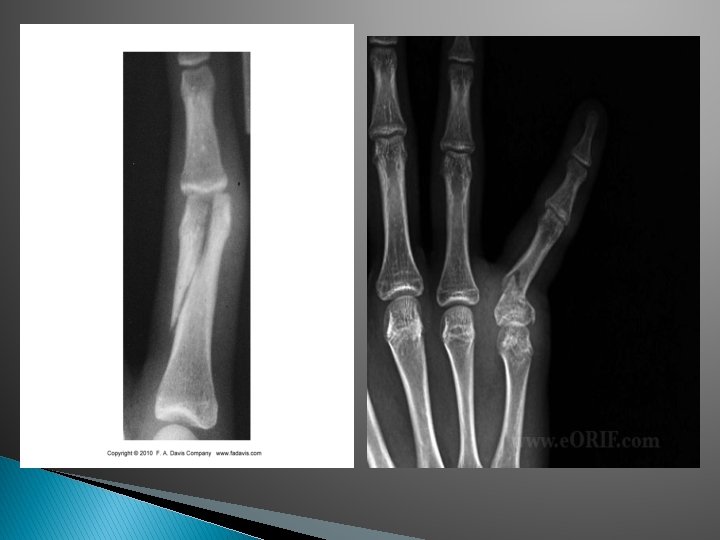

Phalanx Fractures � Fractures common of distal phalanx are the most ◦ MOI is usually direct trauma, shear force or crushing force ◦ S&S include �Gross deformity, swelling, inability to move finger, heard and felt a snap, crepitus ◦ Tx �Splint, surgical intervention

Finger Dislocations � Very common in contact sports and basketball ◦ ALWAYS CHECK FOR AN OPEN DISLOCATION ◦ DO NOT relocate as a student �DO NOT relocate a thumb! ◦ MOI: �Direct truama, shear force ◦ S&S �Gross deformity, pain and inability to move joint ◦ Tx �Reduce (if possible), splint and refer for x-ray (good chance it’s fractured)